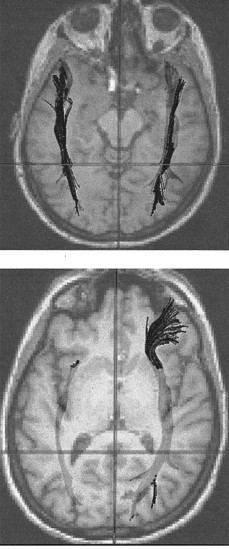

En 2006, participé en un estudio realizado en el Centro de Estudios de Imagen Cerebral de Pittsburgh y me sometí a un escáner de IRM y una versión de la tecnología IRM llamada imagen con tensor de difusión (ITD). La IRMf registra las zonas del cerebro que se iluminan; en cambio, la ITD mide el movimiento de las moléculas del agua a través de los tractos de sustancia blanca (las comunicaciones interdepartamentales de las diferentes zonas).

• El escáner de ITD analizaba los tractos de fibra blanca entre las diversas regiones de mi cerebro. Las imágenes indicaban que estoy hiperconectada, lo cual significa que mi fascículo frontoccipital inferior (FFOI) y mi fascículo longitudinal inferior (FLI) —dos tractos de fibra blanca que serpentean a través del cerebro— tienen muchas más conexiones de lo normal. Cuando recibí los resultados de ese estudio, enseguida me di cuenta de que corroboraban algo que llevaba diciendo hacía mucho tiempo: que debo de tener una línea troncal de Internet, una línea directa, en la corteza visual, lo cual explicaría mi memoria visual. Pensaba que hablaba de forma metafórica, pero en ese momento me percaté de que esta descripción era una explicación exacta de lo que realmente ocurría dentro de mi cabeza. Me puse a buscar estudios sobre cerebro dañado para ver qué más podía averiguar sobre esta línea troncal, y encontré uno en el que participaba una mujer de cuarenta y siete años con perturbación de la memoria visual.2 El escáner ITD de su cerebro revelaba que la mujer tenía una desconexión parcial en su FLI. Los investigadores concluían que el FLI tenía que estar «altamente implicado» en la memoria visual. Recuerdo que pensé: «Si se me rompe este circuito, voy a quedar hecha un auténtico lío».

En estos escáneres de 2006 destacan (las zonas de color negro que van de arriba abajo) mi fascículo longitudinal inferior (FLI) y mi fascículo frontoccipital inferior (FFOI). El FLI es mucho más grueso que el que se vería en un cerebro normal, y se pueden observar fácilmente las muchas ramificaciones de mi FFOI. En ambos casos, estos tractos de sustancia blanca se extienden hasta la corteza visual primaria, lo cual quizás explique en parte mi extraordinaria memoria visual. © Doctora Marlene Behrmann, Brain Imaging Research Center, Carnegie Mellon University, Pittsburgh.

Este escáner realizado en la Universidad de Utah en 2010 muestra de forma contundente que mi ventrículo izquierdo es mucho más largo que el derecho —un 57% más largo—. Es tan largo que penetra en el interior de la corteza parietal, un área que se asocia a la memoria a corto plazo, lo cual tal vez explique mi escasa capacidad para recordar varias informaciones dadas a intervalos muy cortos. © Jason Cooperrider.